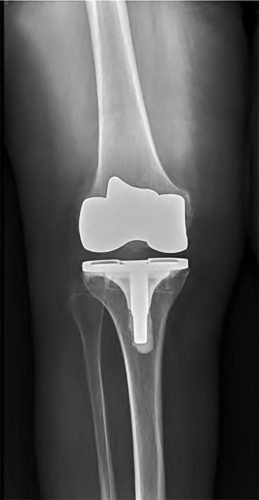

A 64-year-old woman with osteoarthritis underwent bilateral total knee replacement 3 years ago. Current radiographs are shown in Figure A. She reports a 3-month history of bilateral knee pain while at rest and increasing swelling in the knees. Her ESR and CRP are elevated and bilateral knee aspiration cultures reveal Staphylococcus aureus. What is the most likely outcome if the patient undergoes simultaneous, bilateral knee resection arthroplasty with cement spacer and a course of intravenous antibiotics?

This patient presents with bilateral total knee arthroplasty infection.

Wolff et al report Level 4 evidence of 18 patients followed an average of 5 years after bilateral TKA infection. Eleven patients were initially treated with attempts to salvage the original prosthesis (polyethylene l liner exchange, I&D, IV antibiotics and chronic oral suppressive antibiotics. With prosthesis retention, 9/11 (81%) developed recurrent infection at a mean of 15 months. The other 10 patients initially underwent resection arthroplasty with cement spacer and a course of IV antibiotics. Seven of the 10 (70%) underwent reimplantation at a mean of 3 months (6 weeks to 5 months) and none of the patients required revision at mean of two years follow up. Satisfaction rates were significantly higher among this group of patients. The authors advocate the protocol of bilateral TKA resection arthroplasty with cement antibiotic spacer and course of IV antibiotics followed by prosthesis reimplantation.